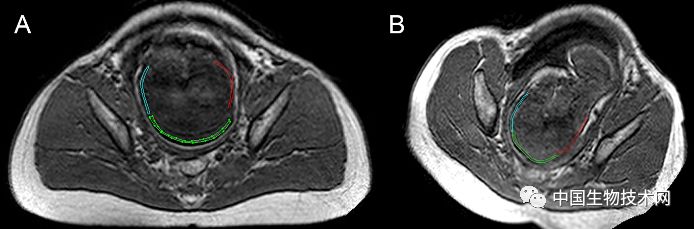

胎头成型和第二产程期间的头部形状变化 图片来源:《PLOS ONE》

近日,法国克莱蒙奥弗涅大学的研究人员利用三维磁共振成像(MRI)技术,拍摄了显示胎儿大脑和头骨在分娩前通过产道时如何改变形状的三维图像。该研究结果近日已发表在《PLOS ONE》上。

众所周知,胎儿头部在出生时是会发生形状改变的,这些变化被称为“胎头成型”,发生在分娩的第二阶段(第二产程)——当胎儿离开子宫通过产道时经历这些变化。然而,研究人员对胎头成型的细节仍知之甚少,只有一项先前的研究曾捕捉到这一过程的图像。

在这项新研究中,为了证明和描述胎头成型和分娩过程中大脑形状的变化,Olivier Ami博士领导的研究团队使用三维MRI捕捉了7名胎儿在分娩前和第二产程中头骨和大脑的详细图像。该分析揭示了所有7名胎儿在第二产程都有胎头成型,其中颅骨的不同部位存在不同程度地重叠。其中5名新生儿的头骨和大脑形状恢复到出生前的态势,但另外2名新生儿的头骨和大脑形状仍在变化。胎头成型程度最高的三名新生儿中有两名是通过紧急剖腹产手术分娩的,另一个是通过阴道分娩的。

图片来源:《PLOS ONE》

总的来说,该研究结果表明,胎儿在出生时承受的颅骨压力比之前所认为的要大,这可能是许多顺产新生儿出现无症状性脑出血和视网膜出血的潜在原因。